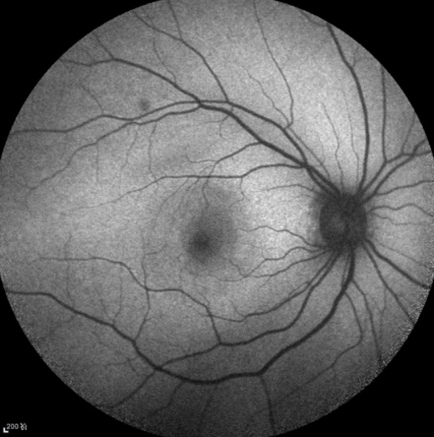

图1 右眼底黄斑中心凹下可见直径约1/5PD大小的视网膜下黄色病灶,伴周围视网膜水肿。颞上血管弓出可见小斑状白色病灶,与棉绒斑类似

Figure 1 On color fundus image, a yellow subretinal lesion with one fifth papillary diameter size complicated with surrouding retinal edma can be seen at the fovea. A small white spot mimicing cotton wool spot can be seen at the supratemporal arch